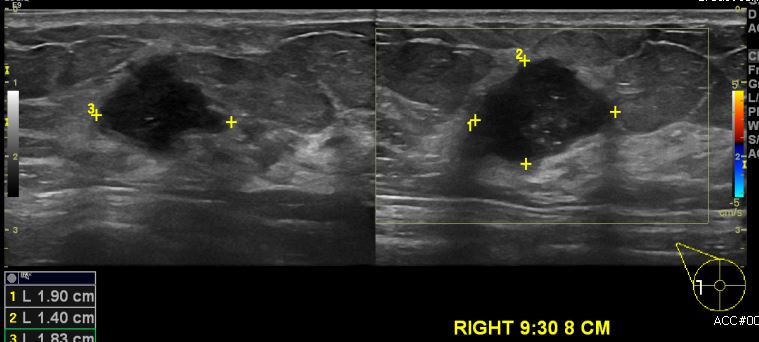

상기 환자 우측 유방에 만져지는 멍우리로 내원하신 40대 여성 분으로

우측 유방 9시 30분 방향 8cm 떨어진 거리의 혹 조직검사 시행하여

우측 침윤성 유관암 진단 되었습니다.